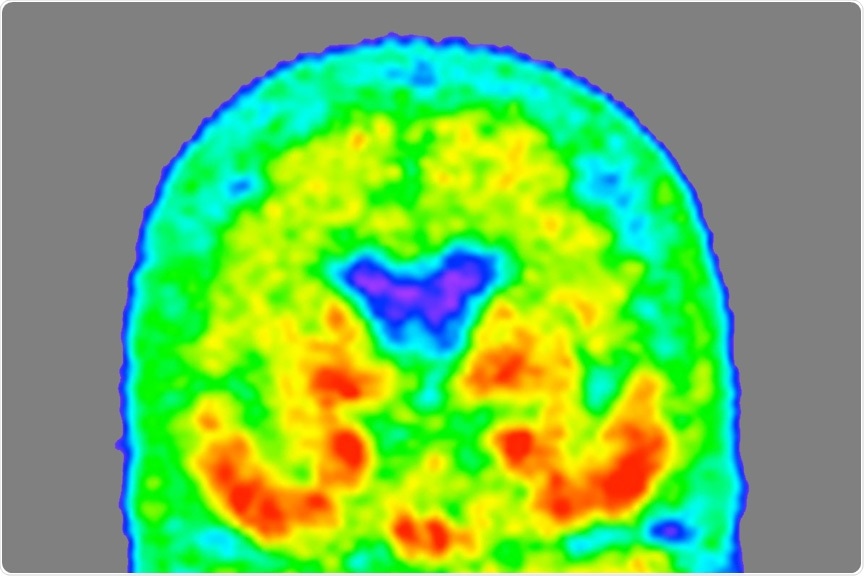

Heat map of tau

Image Credit: Tammie Benzinger/Knight ADRC

Currently, positron emission tomography (PET) scans are required to detect tau tangles in the brain. However, these are time-consuming and expensive. The identification of the MTBR tau fluid biomarker will allow scientists to develop more accessible, cost-effective testing. Bateman and his colleagues are currently working on establishing a diagnostic blood test with the help of this biomarker.